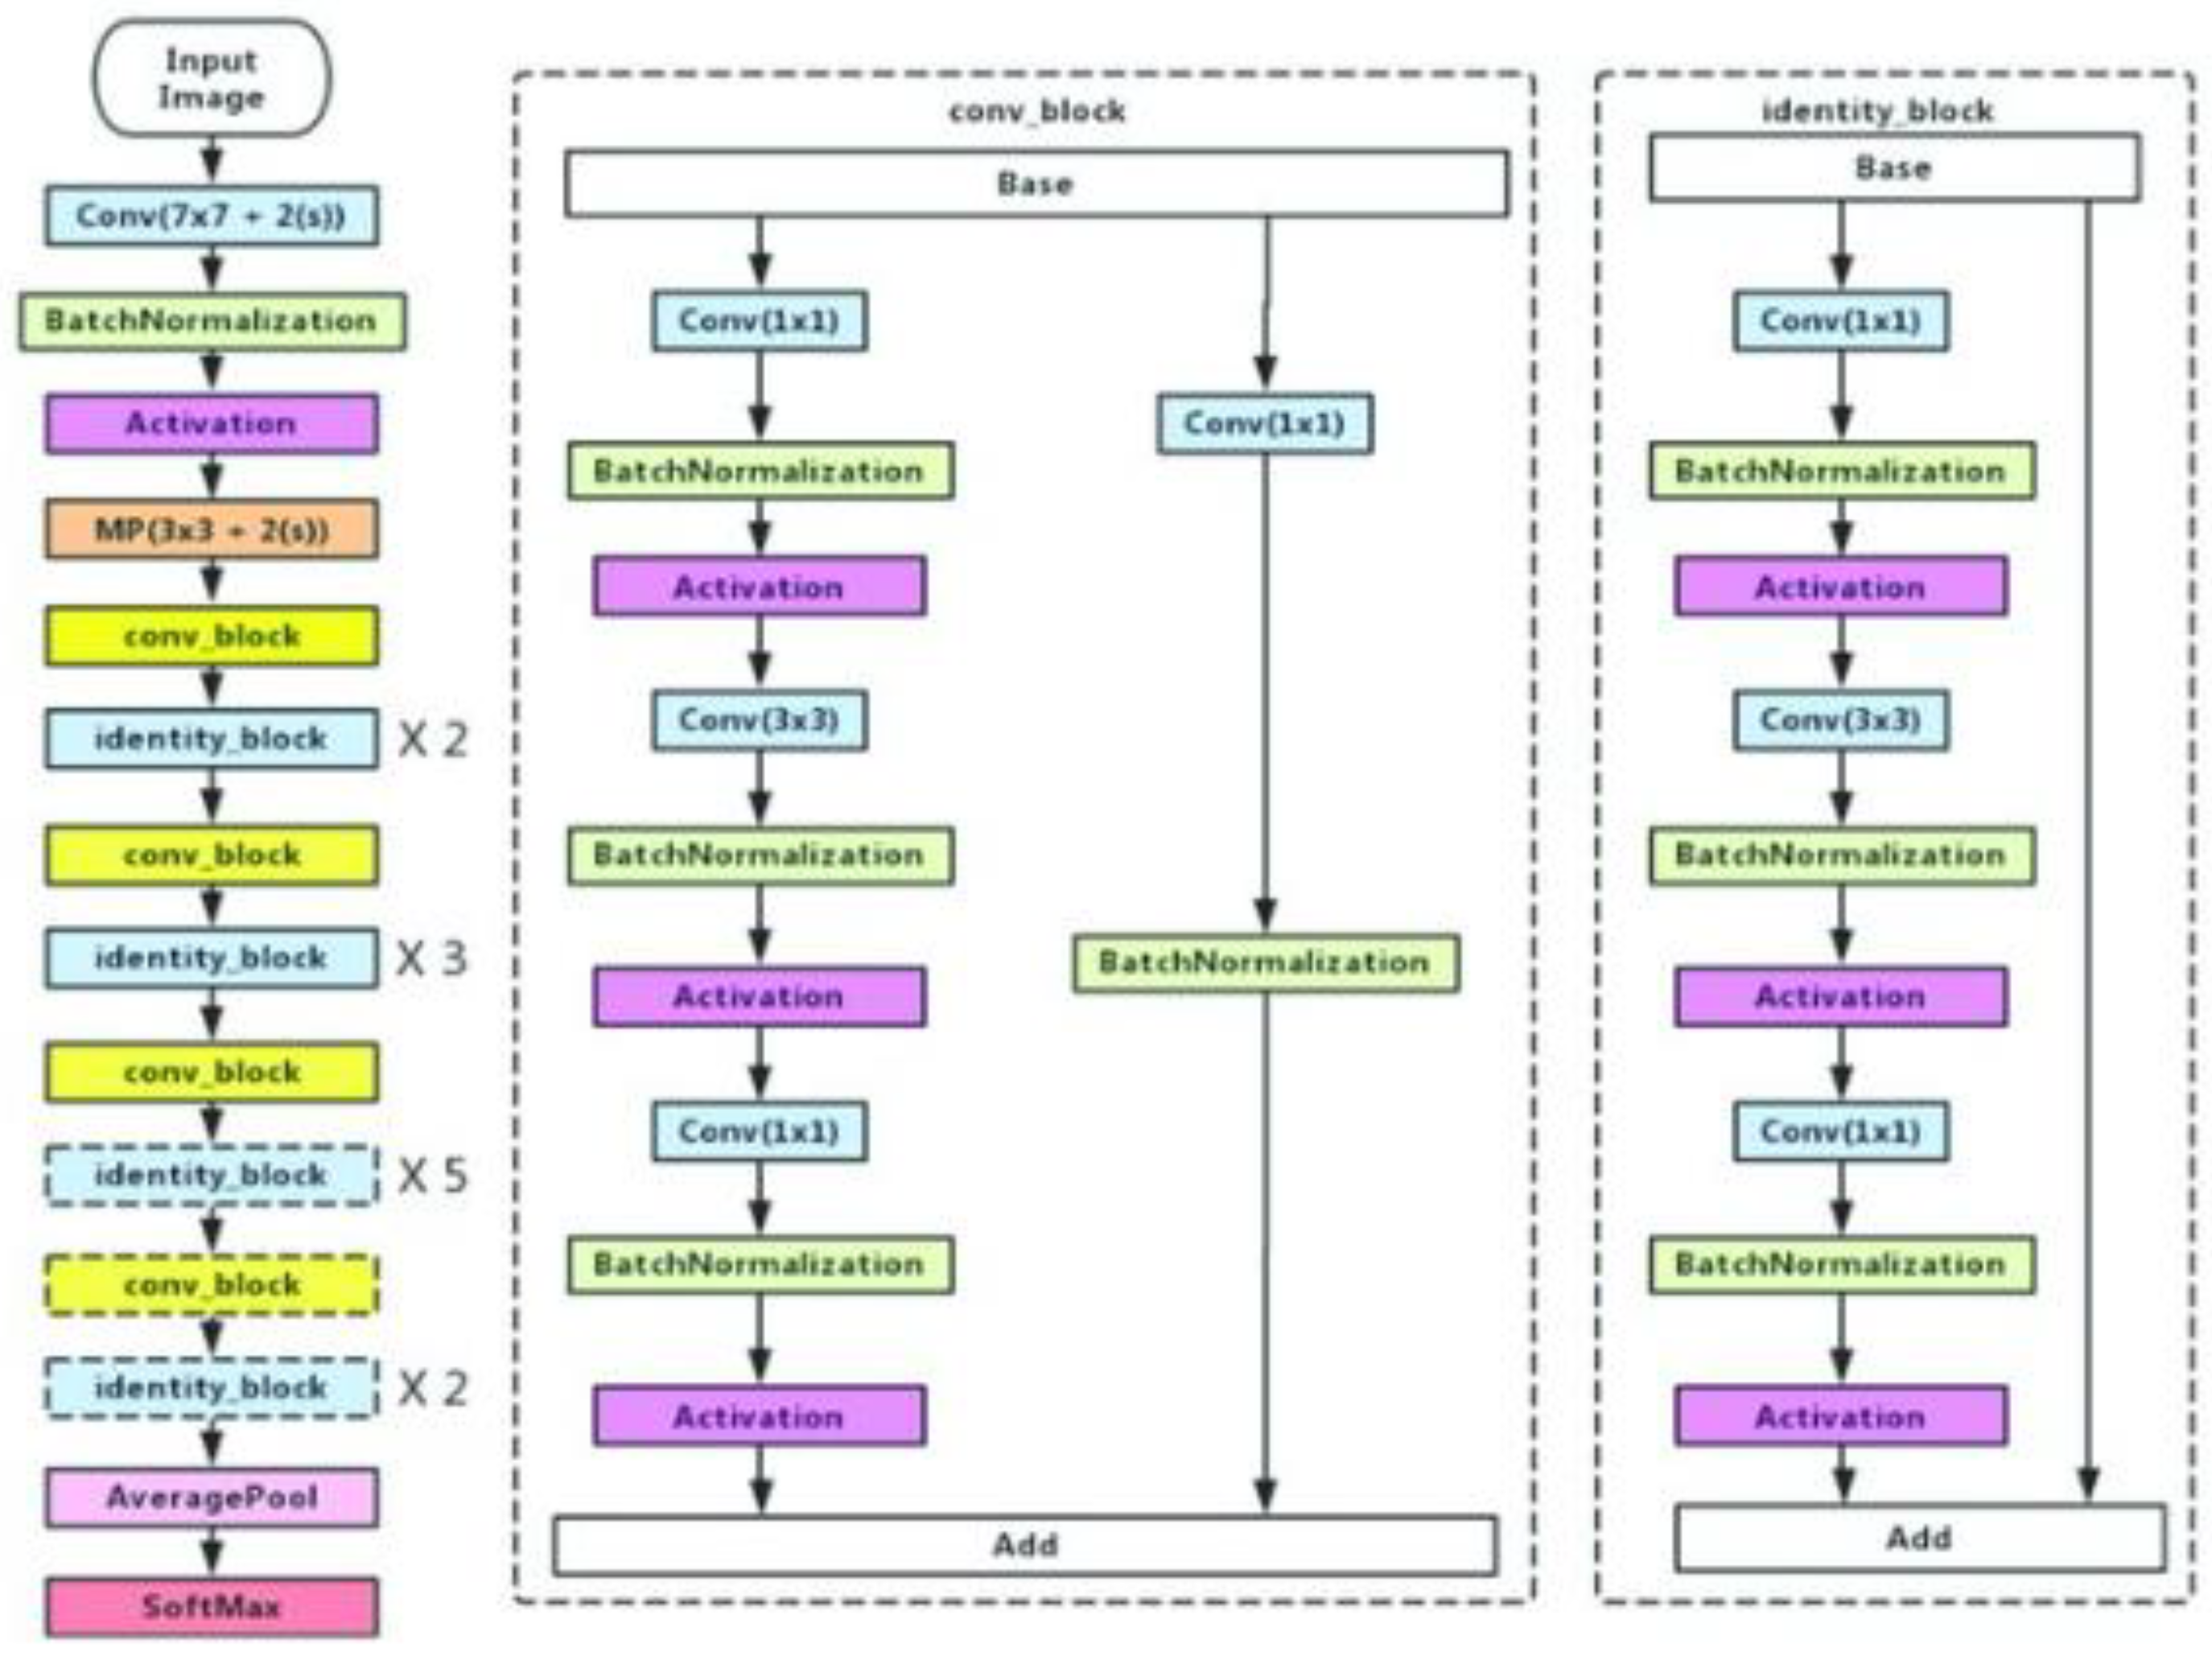

2.2.1. Encoder

Transfer Learning

- ResNet50